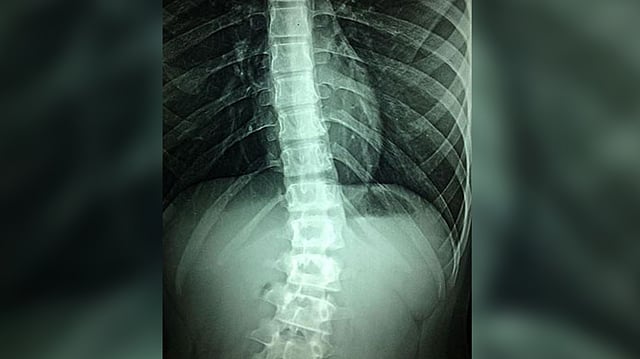

WASHINGTON: Currently, there are no effective treatments for spinal cord injury; physical rehabilitation can help patients regain some mobility, but the outcomes are severely limited in severe cases due to the failure of spinal neurons to regenerate naturally after injury.

Researchers led by Simone Di Giovanni at Imperial College London in the UK show that weekly treatments with an epigenetic activator can aid the regrowth of sensory and motor neurons in the spinal cord when given to mice 12 weeks after severe injury. The findings of the study were published in the journal PLOS Biology.

Building on their past success, researchers used a small molecule called TTK21 to activate genetic programming that induces axon regeneration in neurons.

TTK21 changes the epigenetic state of genes by activating the CBP/p300 family of co-activator proteins. They tested TTK21 treatment in a mouse model of severe spinal cord injury.

The mice lived in an enriched environment that gave them opportunities to be physically active, as is encouraged in human patients. Treatment began 12 weeks after severe spinal cord injury and lasted for 10 weeks. Researchers found several improvements after TTK21 treatment compared with control treatment.

The most noticeable effect was more axon sprouting in the spinal cord. They also found that retraction of motor axons above the point of injury halted, and that sensory axon growth increased.

These changes were likely due to the observed increase in gene expression related to regeneration. The next step will be to enhance these effects even more and to trigger the regenerating axons to reconnect to the rest of the nervous system so that animals can regain their ability to move with ease.

Di Giovanni adds, "This work shows that a drug called TTK21 that is administered systemically once/week after a chronic spinal cord injury (SCI) in animals can promote neuronal regrowth and an increase in synapses that are needed for neuronal transmission. This is important because chronic spinal cord injury is a condition without a cure where neuronal regrowth and repair fail. We are now exploring the combination of this drug with strategies that bridge the spinal cord gap such as biomaterials as possible avenues to improve disability in SCI patients."